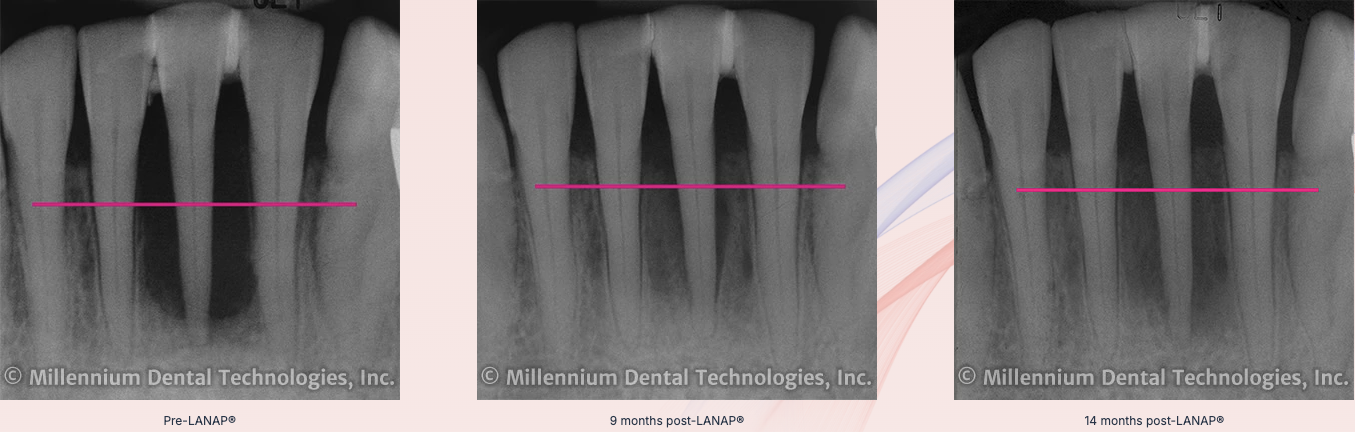

This laser periodontal therapy is especially effective for patients with moderate to severe periodontitis, where untreated infection can lead to gum recession, bone loss, and even tooth loss. By gently eliminating diseased tissue and stimulating the body’s natural healing response, LANAP promotes periodontal regeneration and helps create a stable foundation for long-term oral health. Many patients choose LANAP because it typically involves less discomfort, minimal bleeding, and faster recovery compared to conventional gum surgery.